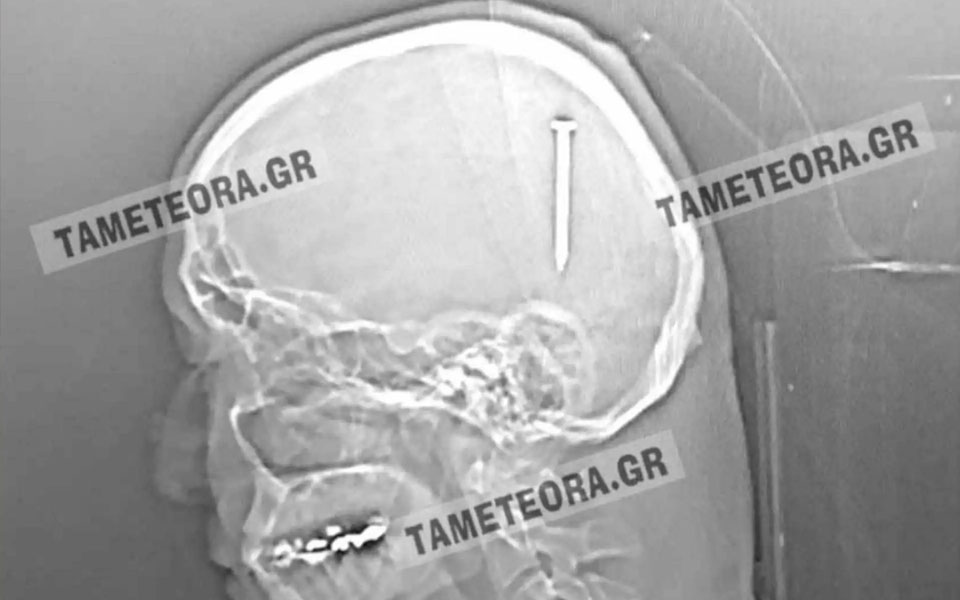

Καλαμπάκα: Του σφηνώθηκε καρφί μέσα στο κεφάλι και όμως επιβίωσε

Όλα συνέβησαν όταν ο πρωταγωνιστής της ιστορίας, κατά τη διάρκεια εργασιών, ένιωσε ένα τράνταγμα, χωρίς όμως πόνο ή κάποιο άλλο σύμπτωμα.